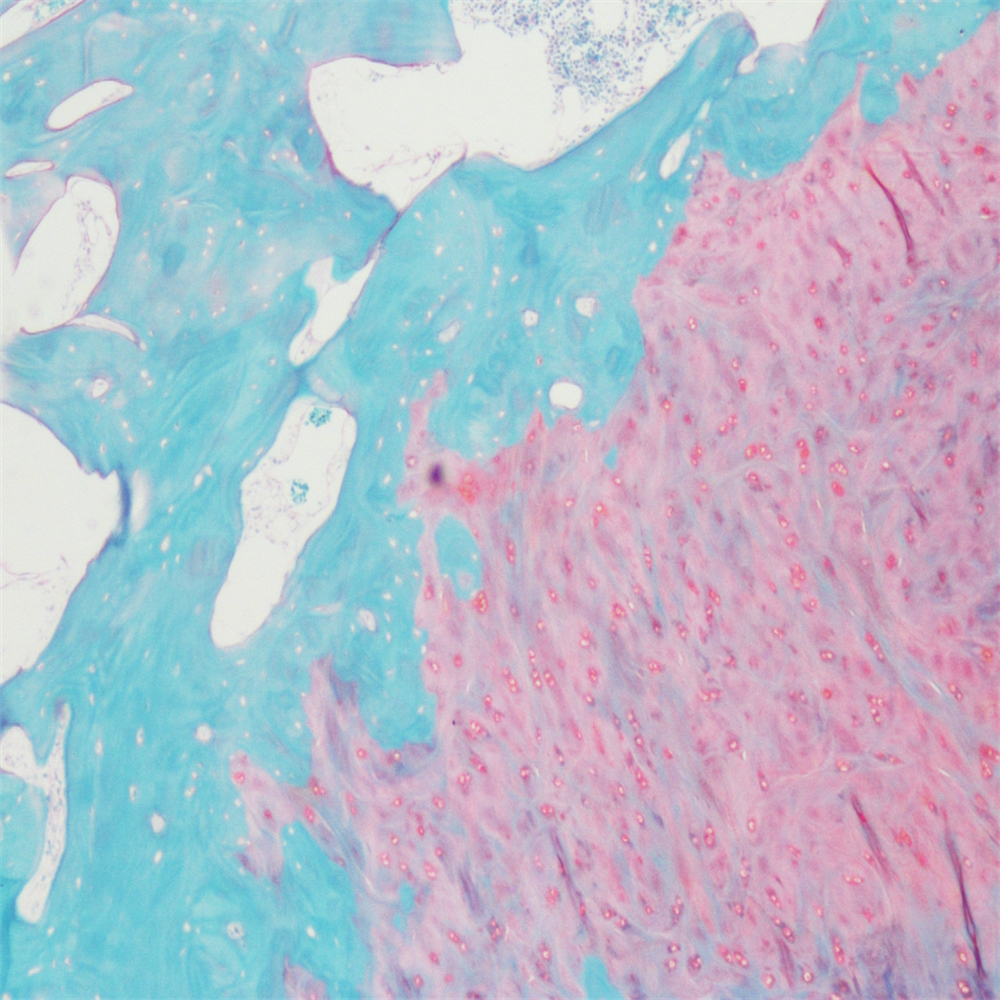

番红-固绿染色

番红-固绿染色(软骨)在涉及关节软骨及软骨下骨的形态学研究中,常需联合使用多种染料以显示其组织学结构。其中,起源于上世纪60年代的番红O(safranin O)-固绿(fast green)染色因可以直观反映关节软骨、软骨下骨和骨组织的结构而备受青睐。软骨呈红色,成骨呈绿色。

番红-固绿(软骨)染色法的染色原理在于嗜碱性的软骨和碱性染料番红O结合呈现红色,嗜酸性的骨和酸性染料固绿结合而成绿色或者蓝色,与呈现红色的软骨对比鲜明,从而将软骨组织和骨组织区分开。番红O是一种结合多阴离子的阳离子染料,其显示软骨组织是基于阳离子染料与多糖中阴离子基团(硫酸软骨素或硫酸角质素)结合。番红O着色与阴离子的浓度近似成正比关系,间接反映基质中蛋白多糖的含量和分布。当软骨收到损伤时,软骨中的糖蛋白会释放出来,使基质成分分布不均匀,从而导致番红O淡染或不着色。通过图像分析软件可以对番红O染色的软骨基质进行定量分析。固绿与胶原纤维结合,不宜褪色。

<<>番红固绿-骨>